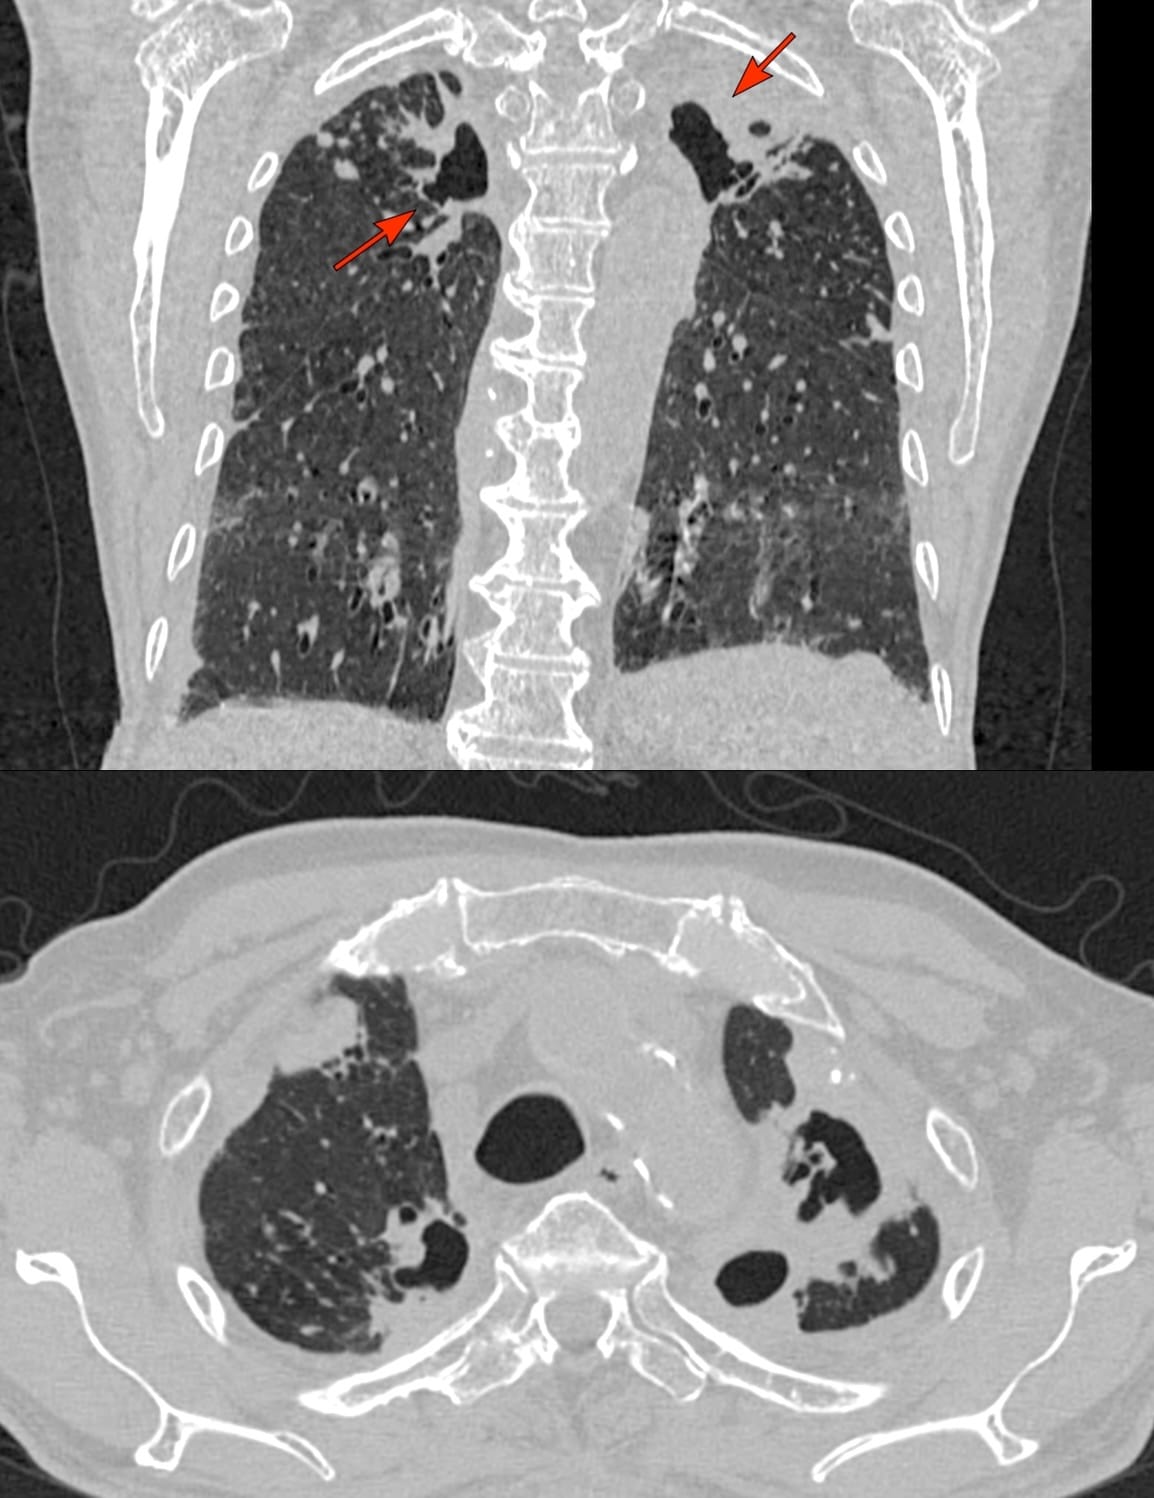

The CT scan showed extensive pleural plaques (arrows), some calcified, some not.

He also had coexistent resolving tuberculosis (on AKT) with fibrocystic and fibrocavitary lesions in the upper lobes (arrows).